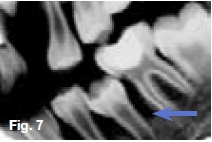

Hypovitaminosis D leads to nondeposition of calcium salt in bone matrix. Figure 5 is a lateral skull radiograph showing generalized radiolucency while figures 6 & 7 are intra-oral and bitewing radiographs of the same patient showing large pulp cavities (green arrow) and attenuation of the lamina dura and dental crypts (yellow arrow). There is also lack of mineralization of the alveolar crest bone (blue arrow). These radiological features are suggestive of Vitamin D-resistant rickets which is an isolated renal tubular defect inhibiting reabsorption of inorganic phosphates, resulting in hypophosphaturia which is inherited as an X-linked dominant trait. The full manifestation of vitamin D-resistant rickets is rickets or osteomalacia non-respondent to vitamin D therapy, as vitamin D metabolism is normal. However, there is diminished intestinal calcium and phosphate absorption. Patients with the milder form may be slightly shorter than normal siblings, with no other manifestation. Females with vitamin D resistant rickets tend to show fewer signs and symptoms than do their brothers.